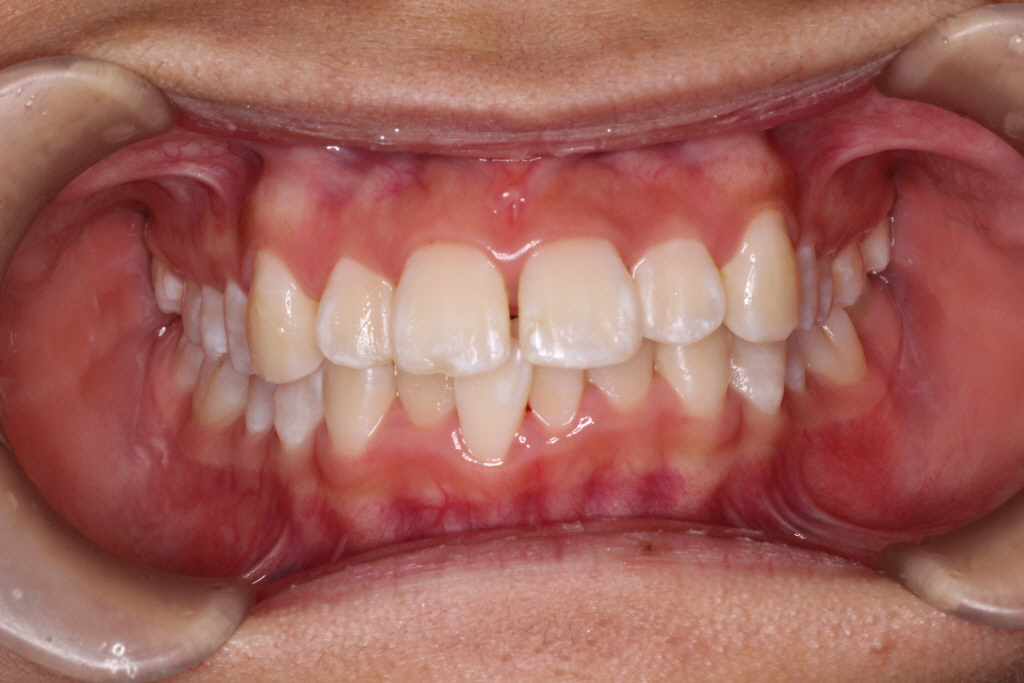

最後のアライナーが終わった時の口腔内写真です。

前歯のがたつきはなくなり、カリエール後にできていた隙間もなくなっています。

奥歯も1歯対2歯の関係で咬めていることがわかります。

通常は歯の並びを微調整するために口腔内を再スキャンし、歯の並びを再設計すること(リファイメント) を2,3回行いますが今回のケースは一回目で満足のいく結果が得られたのでここで保定期間に入りました。

患者様には気にされていた歯のでこぼこがなくなり、喜んでいただきました。

矯正にかかった期間はなんと1年です。